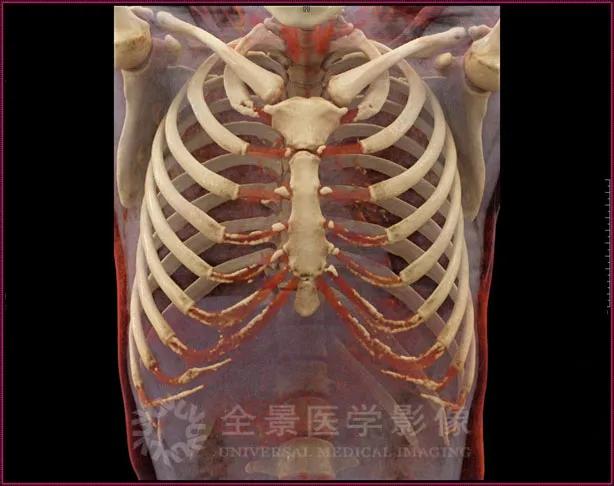

自体肋软骨作为充填、支撑材料在整形手术中应用非常普遍,如鼻整形术、耳廓再造术及阴茎再造术等。

然而自体肋软骨移植也有其固有局限性,如术前无法准确评估肋软骨的形态,以及无法准确评估肋软骨的钙化程度等。

这些问题都是手术过程中切取肋软骨存在一定的盲目性与局限性,如钙化会引起肋软骨生物力学性能的改变,严重的肋软骨钙化就不建议做自体肋软骨隆鼻手术。

cVRT 影像重建图

25 岁,男性,可见双侧肋软骨少许钙化

21 岁,女性,可见双侧肋软骨多发明显钙化

cinematic VRT 是在传统容积重建技术(VRT)基础上,利用仿生成像技术以及运用人工技能的光学模型算法,更好显示组织结构在三维图像上的细节,可以直观、精确显示肋软骨的形态及钙化情况,为术前评估肋软骨提供良好的证据。